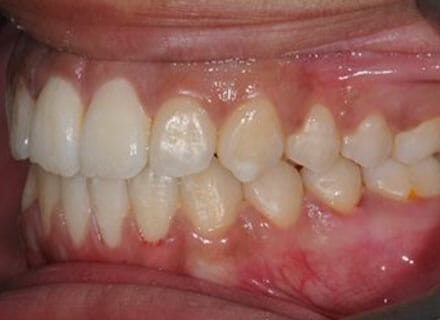

This patient came to us because she hated her smile: it was too narrow, the upper front teeth were all crowded into each other and twisted. She couldn’t eat a sandwich properly with the front teeth because of the gap – the open bite. We were able to expand both jaws to make space to align all the teeth without having to extract – in about 18 months using clear brackets.